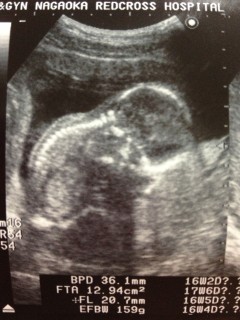

腹部エコーで、前回同様手を挙げて元気アピールしてくれました! 先生が「手を撮りたいなー」って言ってたら、手を挙げてくれました。 検診日の朝に初胎動で、先生に確認したところ初産の人は気付きにくいんだけど、エコー見ても元気だねー。と言ってくれました。 毎日胎動が楽しみです。

お腹がぽっこりしていてとっても可愛いです。手を耳の方に持ってきています♪